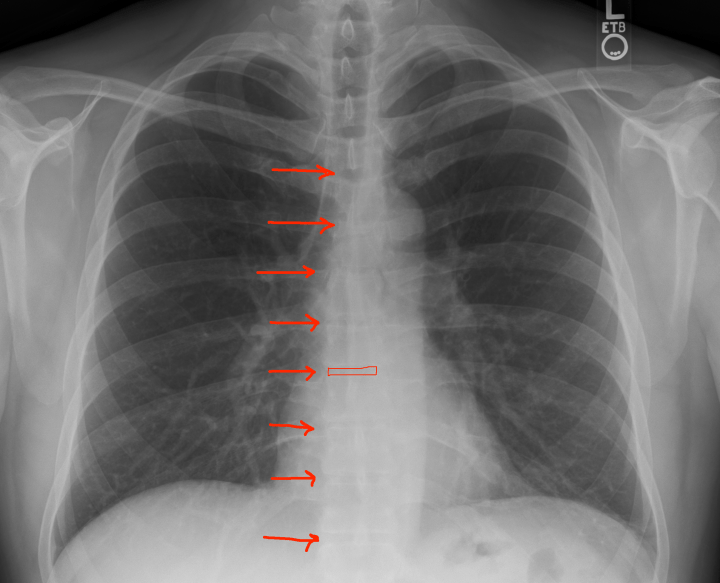

- Inspiration: Did the patient take an adequate breath? Count the ribs from top to bottom and see how many ribs you see before they dive under the diaphragm. >7 is the magic number. Less and you’re going to struggle to see enough of the chest cavity to make an accurate diagnosis. For some patients, elderly/frail/smokers, that’s all you’re going to get. Good luck. I would dictate this as “adequate/full inspiration”.